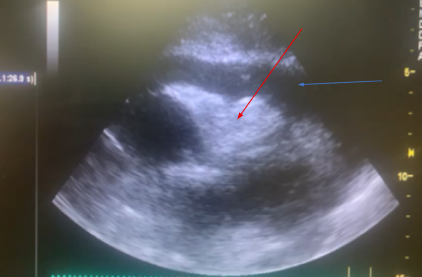

Ecocardiograma é uma importante ferramenta no diagnóstico da ruptura de parede livre bem como do tamponamento cardíaco, fornecendo as informações citadas a seguir, bem como podemos observar em (A) e (B):

A: derrame pericárdico (seta azul) e colabamento do VD (seta vermelha)